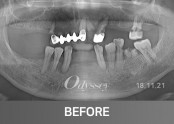

임플란트 181208